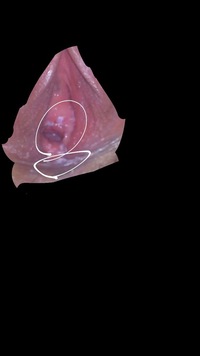

子宮膣部びらん 名古屋 栄 ともこレディースクリニック

子宮頚管ポリープとは 名古屋 栄 ともこレディースクリニック

膣ポリープ 丹沢の森どうぶつ病院

高橋ペットクリニック ブログ 膣ポリープ

子宮頸管ポリープ ポリープ切除術 膣ポリープ まりこクリニック 京都 滋賀

膣マス 相模原の犬猫専門動物病院 まみや動物病院